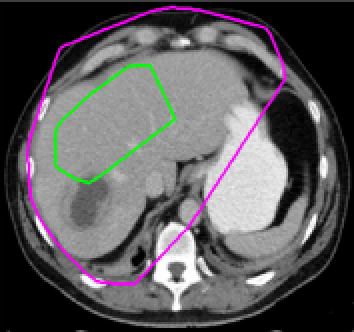

Test 3 – Further Results from the Geodesic Model M7. In this test we give some medical segmentation results obtained using the Geodesic Model M7. The results are shown in Figure 14. In the final two columns we use anti-markers to demonstrate how to overcome blurred edges and low contrast edges in an image. These are challenging and it is pleasing to see the correctly segmented results.

(i) (ii) (iii) (iv) (v)